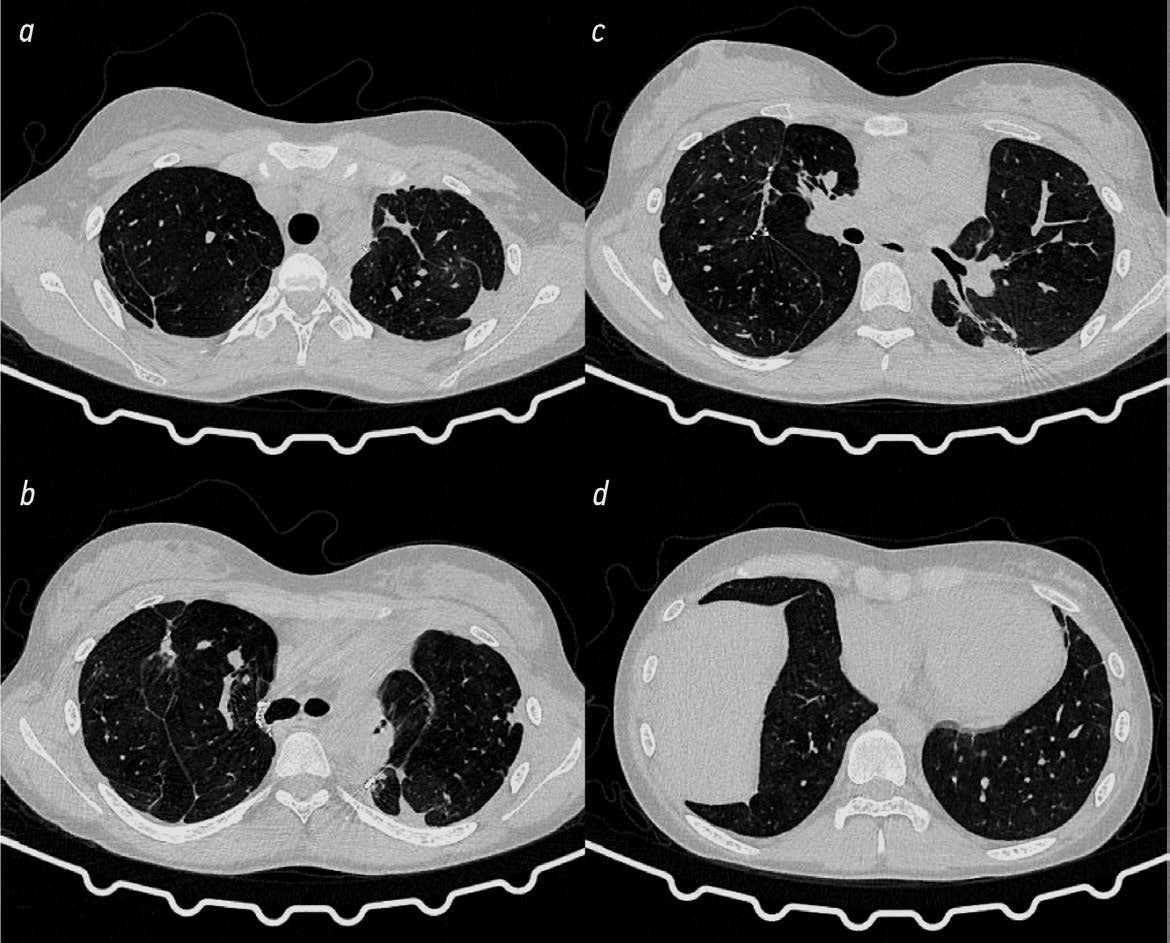

Верхние доли и SVI обоих лёгких уменьшены в объёме. Просветы трахеи и главных бронхов не изменены.

Правое лёгкое. В верхней доле определяются множественные разнокалиберные воздушные полости, участки пневмосклероза с мелкими бронхоэктазами (рис. 1, a). Аналогичные изменения имеются в апикальной части SVI (рис. 1, c), где размеры наиболее крупной полости составляют 44×46×46 мм. В SVIII (рис. 1, d) субплеврально — тонко- стенная полость 18×17×20 мм с мелкими кальцинатами в стенке. Вентиляция сохранной лёгочной ткани неравномерная за счёт участков панлобулярной эмфиземы. Во всех сегментах рассеянные плотные очаги.

Рис. 1. Компьютерная томография органов грудной клетки при поступлении: фиброзно-кавернозный туберкулёз лёгких с гигантскими кавернами в обоих лёгких — SI–III, VI, VIII справа и SI, II, VI слева (описание в тексте).

Fig. 1. Computed tomography of the chest organs upon admission: fibrous-cavernous pulmonary tuberculosis, giant cavities in both lungs — SI–III, VI, VIII on the right and SI, II, VI on the left (description in the text).

Левое лёгкое. В SI–III (рис. 1, a) и апикальной части SVI (рис. 1, b) определяются множественные разнокалиберные воздушные полости, участки пневмосклероза с мелкими бронхоэктазами. Каверны в SII 60×54×63 мм (рис. 1, a). Парамедиастинально в SI, II участок консолидации 35×20×28 мм с единичными мелкими кальцинатами и участками разрежённой структуры (наиболее вероятно конгломерат лимфатических узлов). В верхней части SVI парамедиастинально полость 36×30×17 мм (рис. 1, b). Во всех сегментах сохраняются рассеянные плотные очаги.

Заключение: КТ-признаки ФКТ лёгких в фазе обсеменения — SI–III, VI, VIII справа и SI–II, VI слева, с наличием гигантских каверн в обоих лёгких.